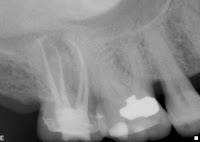

So what exactly is a root canal, you ask? Basically, the inside of your tooth is hollow--from the crown all the way to the ends of the roots. This space inside the tooth is where the nerves and blood supply (pulp) are housed. When the pulp is insulted (usually by decay or trauma) the pulp becomes infected and ultimately dies. Since there is no longer any blood supply inside of the tooth, it becomes a sort of hiding place for bacteria that your immune system cannot reach. This can cause abscess formation, and a chronic inflammatory reaction around the roots where the canals exit and can cause bone destruction, root resorption, etc. So when you do a root canal, you make a hole in the tooth so that you can reach the pulp chamber, you clean and enlarge the canals in the roots, and seal up the roots to keep the bacteria out. Then your immune system can take care of the inflammation/infection that is around the roots. Then you need a filling and usually a crown to fill up the hole and strengthen the tooth against fracture. So in a nutshell, that's what I do every day. Here are some examples of my work: